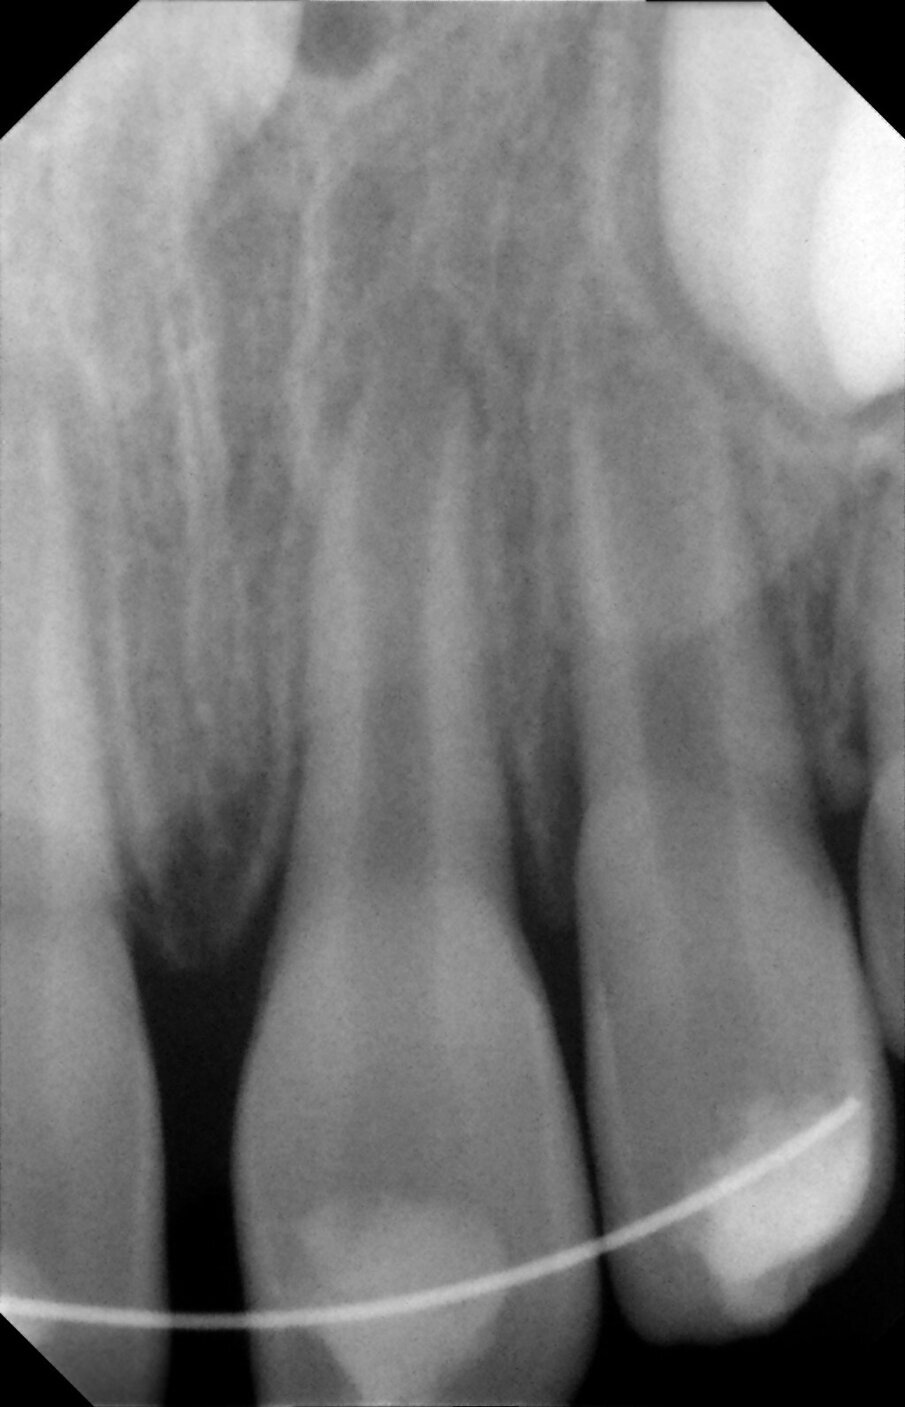

Periapical views of the upper maxillary incisors were obtained to rule out any root fractures (See Figures 4 a & b) revealed immature roots of teeth # 12, 11, 22, no root fractures and an inverted supernumerary apical to 11 and an empty socket of 21. There was no need for soft tissue radiographs as no tooth fragments were missing and the tooth was accounted for.

Figures 4a. Empty socket of 21 due to its avulsion. Notice the immature apices of 12, 11 and 22. In addition there was a supernumerary tooth/mesiodens

Figures 4b. Empy socket of 21 due to its avulsion. Notice the immature apices of 12, 11 and 22. In addition there was a supernumerary tooth/mesiodens